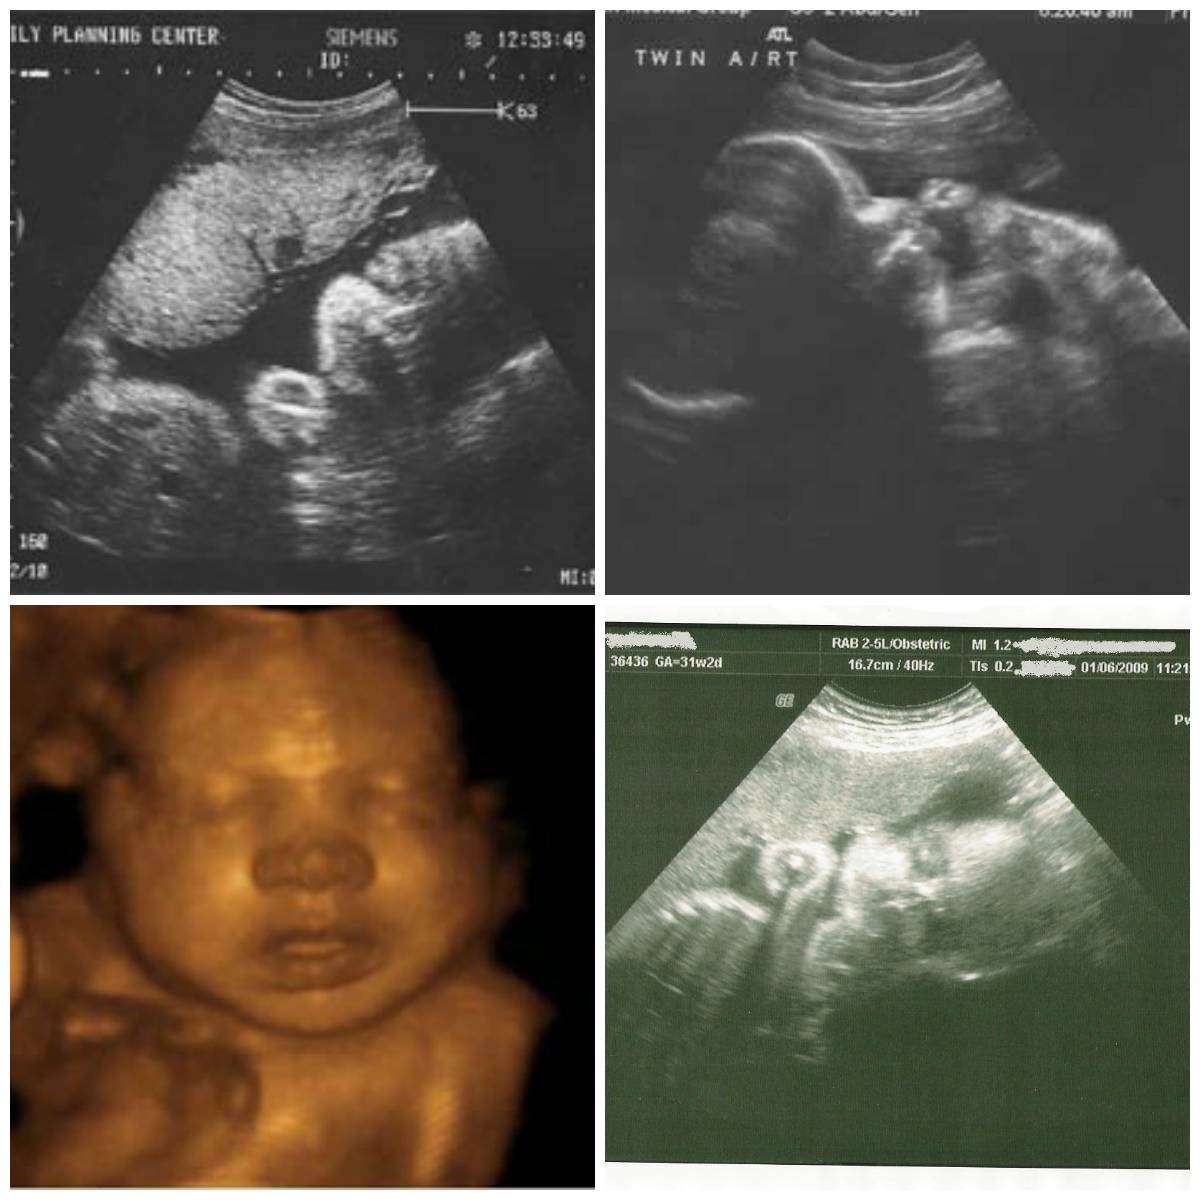

Ошибки на узи при определении пола ребенка Может ли ошибаться узи на пол ребенка

Может ли УЗИ ошибаться с полом ребенка? Это закономерный вопрос, который волнует многих будущих родителей.Большинство хотело бы узнать пол ребенка до его рождения: из статьи вы узнаете, насколько точно это можно сделать с помощью УЗИ, а также найдете друг